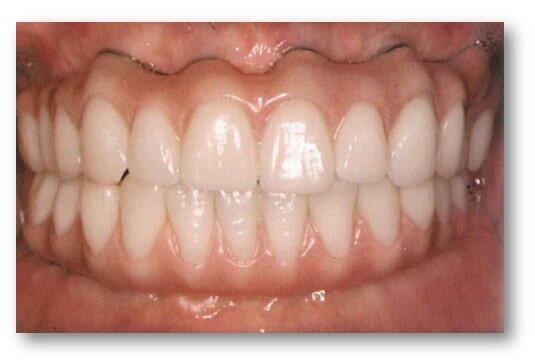

המטרה המשותפת של כל רופאי השיניים מתחומי ההתמחויות השונות היא לשקם למטופל את השיניים על מנת לאפשר פונקציה (אכילה ודיבור) ואסתטיקה. הרופא המשקם (רופא שיניים כללי או מומחה לשיקום הפה) הוא זה שיבנה לבסוף את השיניים החדשות על ידי כתרים וגשרים שנתמכים בשיניים עצמן, על ידי כתרים וגשרים שמורכבים על גבי שתלים דנטליים או על ידי תותבות.